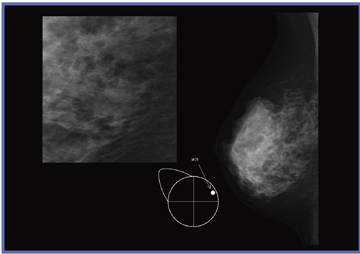

当初は,画像上に重ねてマーカーを入れていたが,読影する医師に先入観を与える可能性があるという指摘があった。そこで,医師に新しいマーカーを考案してもらい,メーカーに作成してもらった(図1)。具体的には,乳房の領域を示すモデル(a)と,画像上でそのまま大きさを比較できるように大きさを5mm(b),10mm(c)とした,ほくろやいぼを示すマーカー,手術瘢痕の形状を示すための5mmの十字マーカー(d)である。当センターではこれらのマーカーを使用することにした(サイズは実寸表示した場合の大きさ)。

図2は,ほくろの入力例である。右A領域にほくろがあったことがマーカーで示されており,画像上に認められる結節がほくろと一致するかを,読影医が判断することができる。図3は,いぼの入力例である。これまでは,コメントを記載するだけで,詳細な大きさや位置を伝えられずにいたが,マーカーの使用により,視覚的な判断が容易となる。また,図4は手術瘢痕の入力例である。以前は構築の乱れに合わせて画像上にマーカーを重ねていたが,新しいマーカーを使用することで,読影医は先入観を持たずに観察でき,技師の示した所見は参考情報として考慮することができるようになった。十字マーカーは1つずつ入力可能なため,直線や円弧状,乳輪に沿った形など自由に記載でき,ニュアンスを伝えやすい。